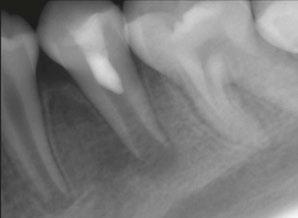

Figure 6 (left): Preoperative image of tooth No. 30. Figure 7 (right): Postoperative image. Rotary negotiation with Roto-reciprocation in all 4 canals and the ProTaper Ultimate Slider advanced to WL within 2 passes without the use of a hand file

After conducting research with the ProTaper Ultimate Slider and successfully negotiating to patency 80% of the time, I then experimented with a hybridized shaping system consisting of using the ProTaper Gold Shaper 1 (Dentspy Sirona) to prepare the middle 1/3 shape, and then following that with reciprocation using the WaveOne Gold Primary (Dentsply Sirona) to finish the apical shape. If a canal had a larger foramen than a No. 25 (tip size of the WaveOne Gold Primary), then I would “upshape” or “plus it” to a WaveOne Gold Medium (No. 35 tip).

In closing, the ProTaper Ultimate Slider has completely changed the way I negotiate to the apex. In over 1,300 cases I have been successful at reaching the apex and beyond 80% of the time. In the majority of these cases, I am able to negotiate to

patency, achieve an accurate working length, and an open glide path (three key endodontic pillars) in seconds. I then follow this up with a hybridized roto-reciprocation technique using the ProTaper Gold S1 to shape the middle third and then the WaveOne Gold Primary to shape the apical third. This roto-reciprocation technique also shapes the majority of canals in just minutes. I now have plenty of time to activate and enhance irrigation with different devices on the market or let the sodium hypochlorite or Triton (Brasseler USA) soak in the canals while I am diagnosing and anesthetizing another patient. All in all, I have been using this new hybridized roto-reciprocation technique for the last year and a half, and it has increased my shaping efficiency, simplified my technique, and has made root canal therapy enjoyable.